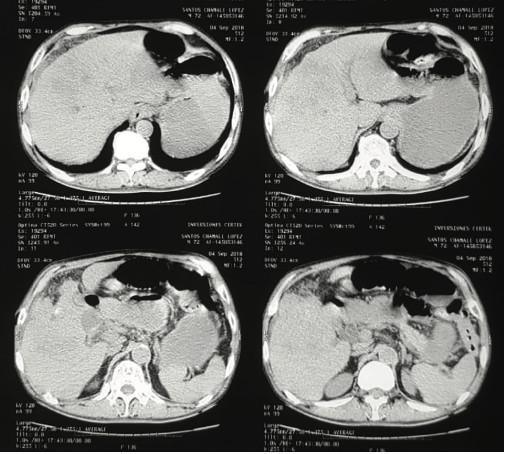

Paciente masculino de 72 años, sin antecedentes médi- cos ni quirúrgicos, que consulta por distensión abdominal de 5 días de evolución, asociado a vómitos con contenido biliar, que previamente ha consultado con medico parti- cular quien por dolor abdominal le solicito USG reportan- do masa en segmento IV hepático por lo cual lo refiere. Al ingreso signos vitales sin alteraciones, con signos de deshidratación, abdomen distendido sin ruidos gastroin- testinales, tacto rectal con heces en ampolla rectal, por lo que se ingresa con diagnóstico de obstrucción intestinal y lesión hepática a estudio iniciando manejo médico, solici- tando laboratorios y estudios de imagen (Figura 1).

Laboratorios de ingreso con leucocitosis (13,500) y for- mula diferencial con neutrofilia (92%), química sanguínea sin alteración hidroelectrolítica, con bilirrubinas totales en 2.1 directa en 1.6 indirecta en 0.5, GGT en 560. A las 6 horas de ingreso distensión mejora y logra defecar por lo que continua en observación. A las 12 horas del ingreso paciente vuelve a distenderse y presentar vómitos por lo que se realiza tac abdominal (Figuras 2 y 3).

Figura 2. Tomografía abdominal que demuestra a nivel hepático neumo- bilia, además no se logra diferenciar adecuadamente lecho vesicular ni vía biliar, únicamente imágenes de infiltración a nivel de lecho hepático.